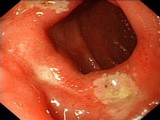

十二指肠球部溃疡

食管炎

溃疡性结肠炎

直肠癌